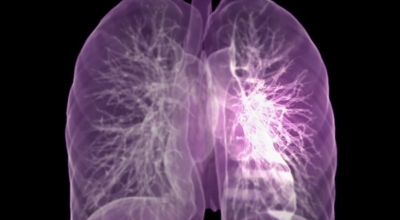

폐에 발생된 악성 종양을 말하며 오랜 기간 흡연해온 남성들에서 발병률이 높고 요즘 들어 가지가지 환경적인 요인의 영향과 간접흡연으로 흡연하지 않는 여성에서도 많이 발생하고 있어요. 증상을 느껴 병원을 찾았을 때는 수술하기 늦은 경우가 많아 사망하는 비율이 매우 높은 암입니다.

폐 자체에서 생기거나 다른 장기에서 발생된 암이 폐로 전이되어 나타나기도 하고 특별한 초기 증상이 없는 경우가 많다고 하며 암이 진행된 후에도 일반적인 감기 증상인 기침과 가래 외의 특이 증상이 나타나지않아 증상만으로는 진단이 쉽지 않아요. 폐암 역시 다른 암들과 마찬가지로 조기 발견 및 치료가 매우 중요하므로 일상 속에서 폐암 초기증상을 간과하지 않도록 주의를 기울여야 해요.